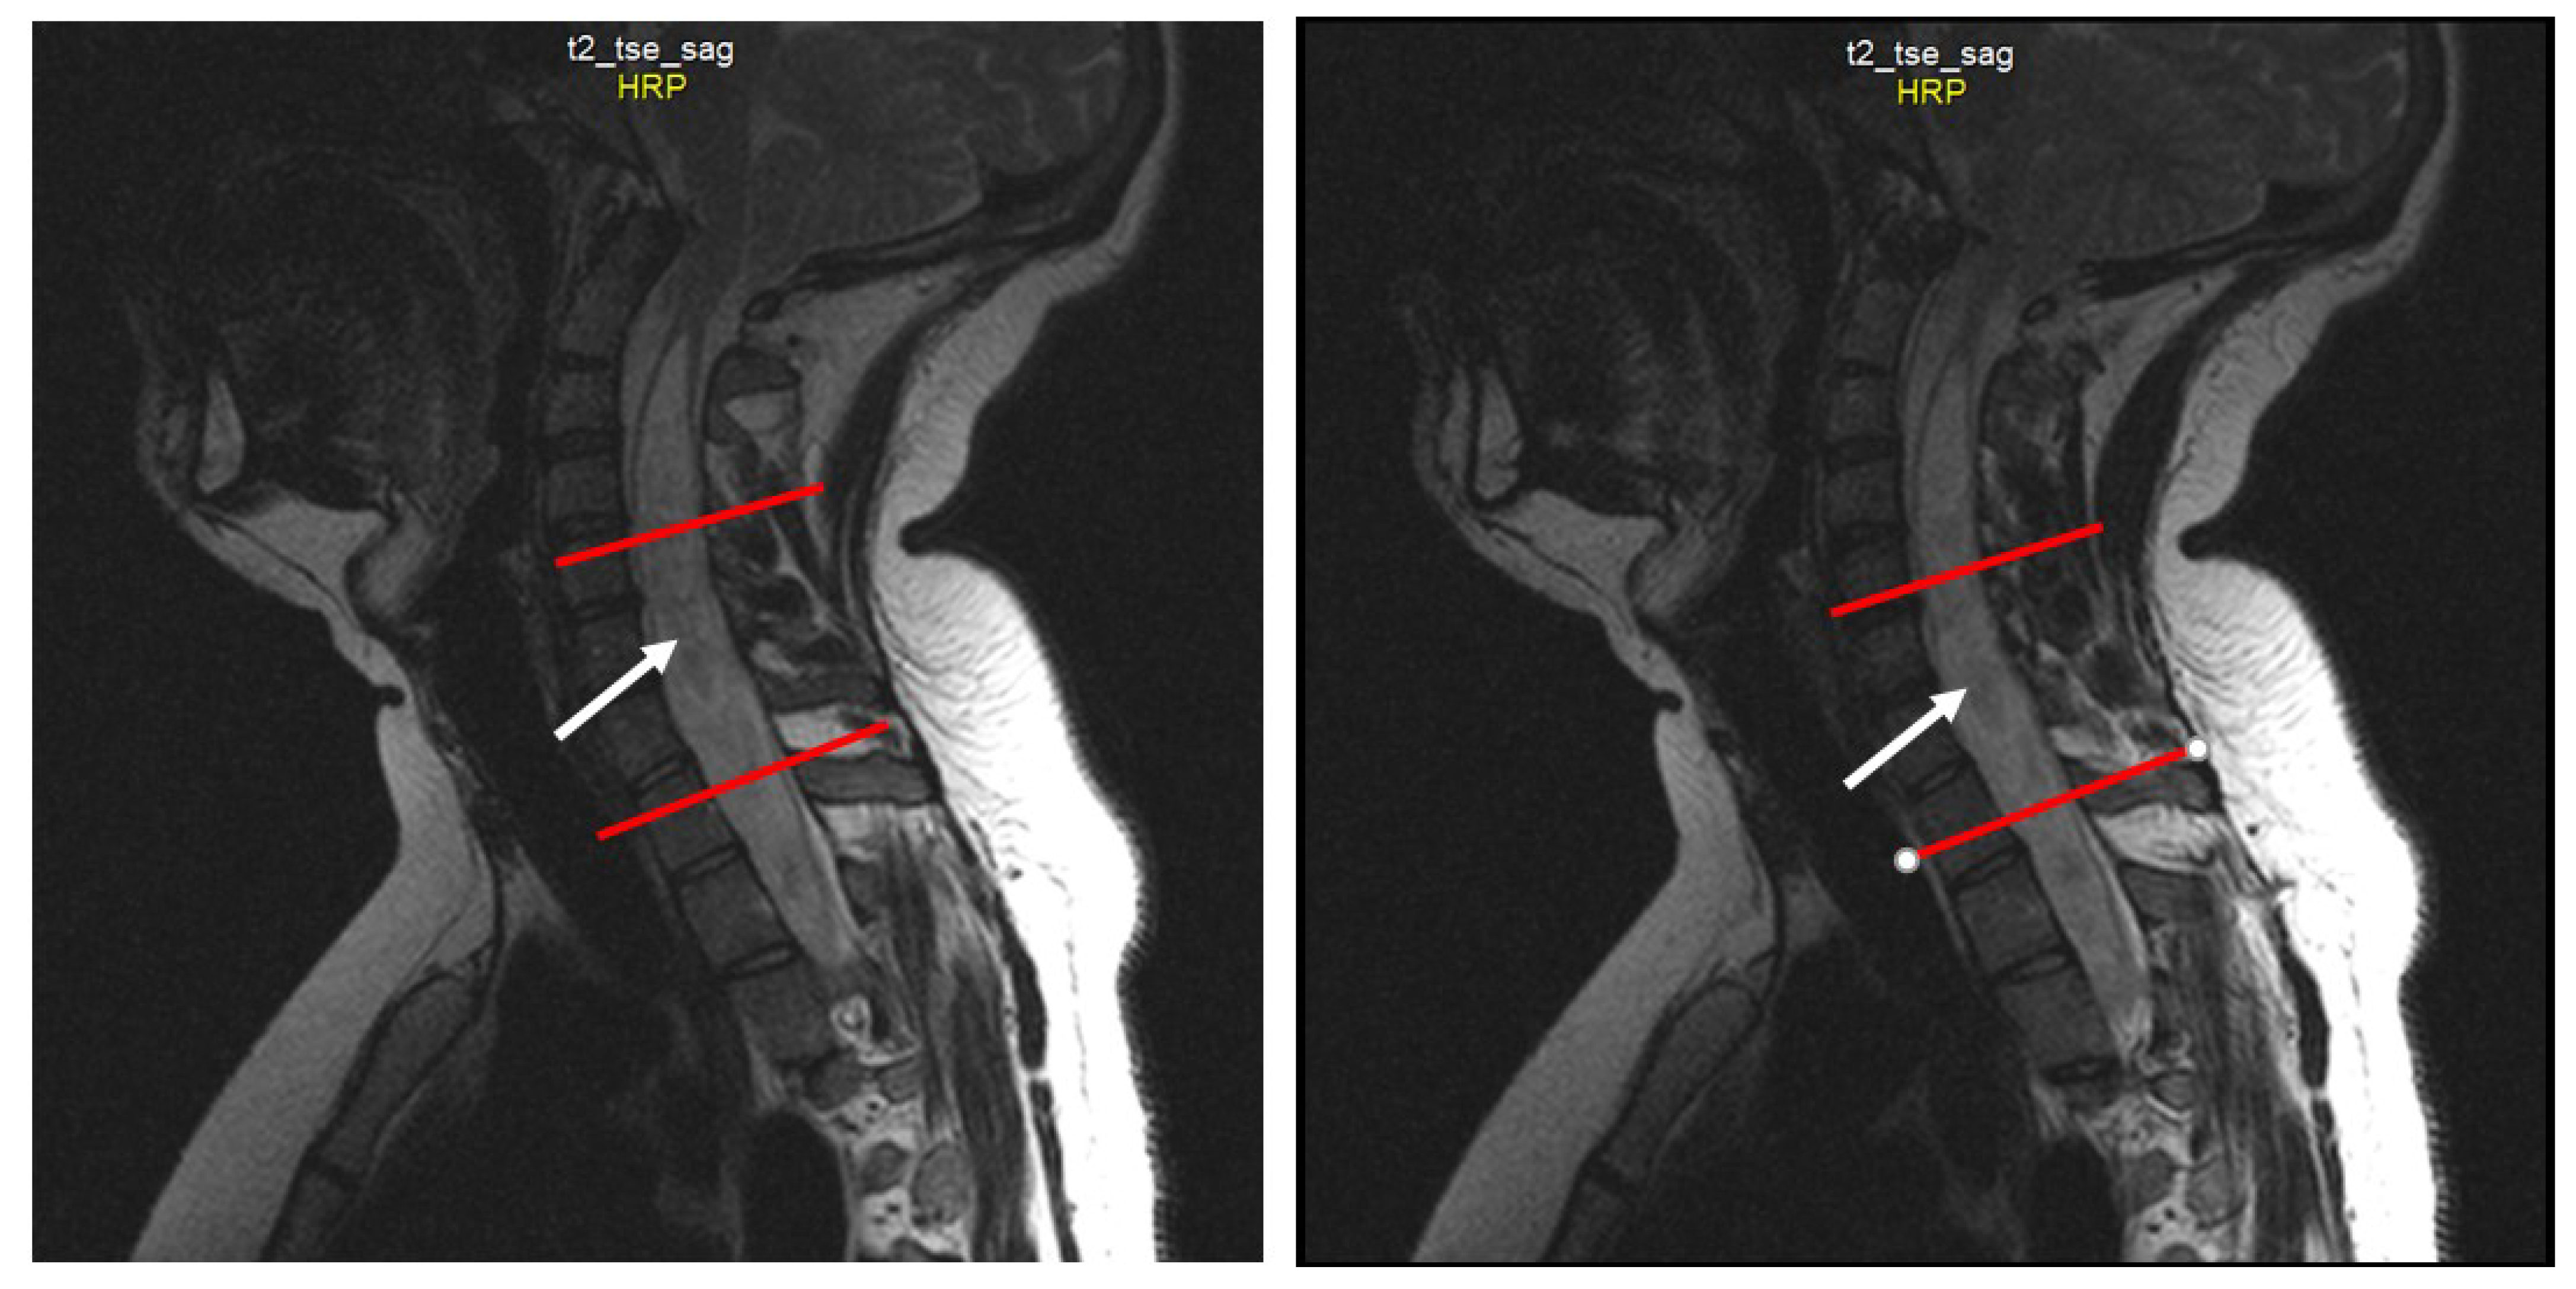

2.4. Neuroimaging